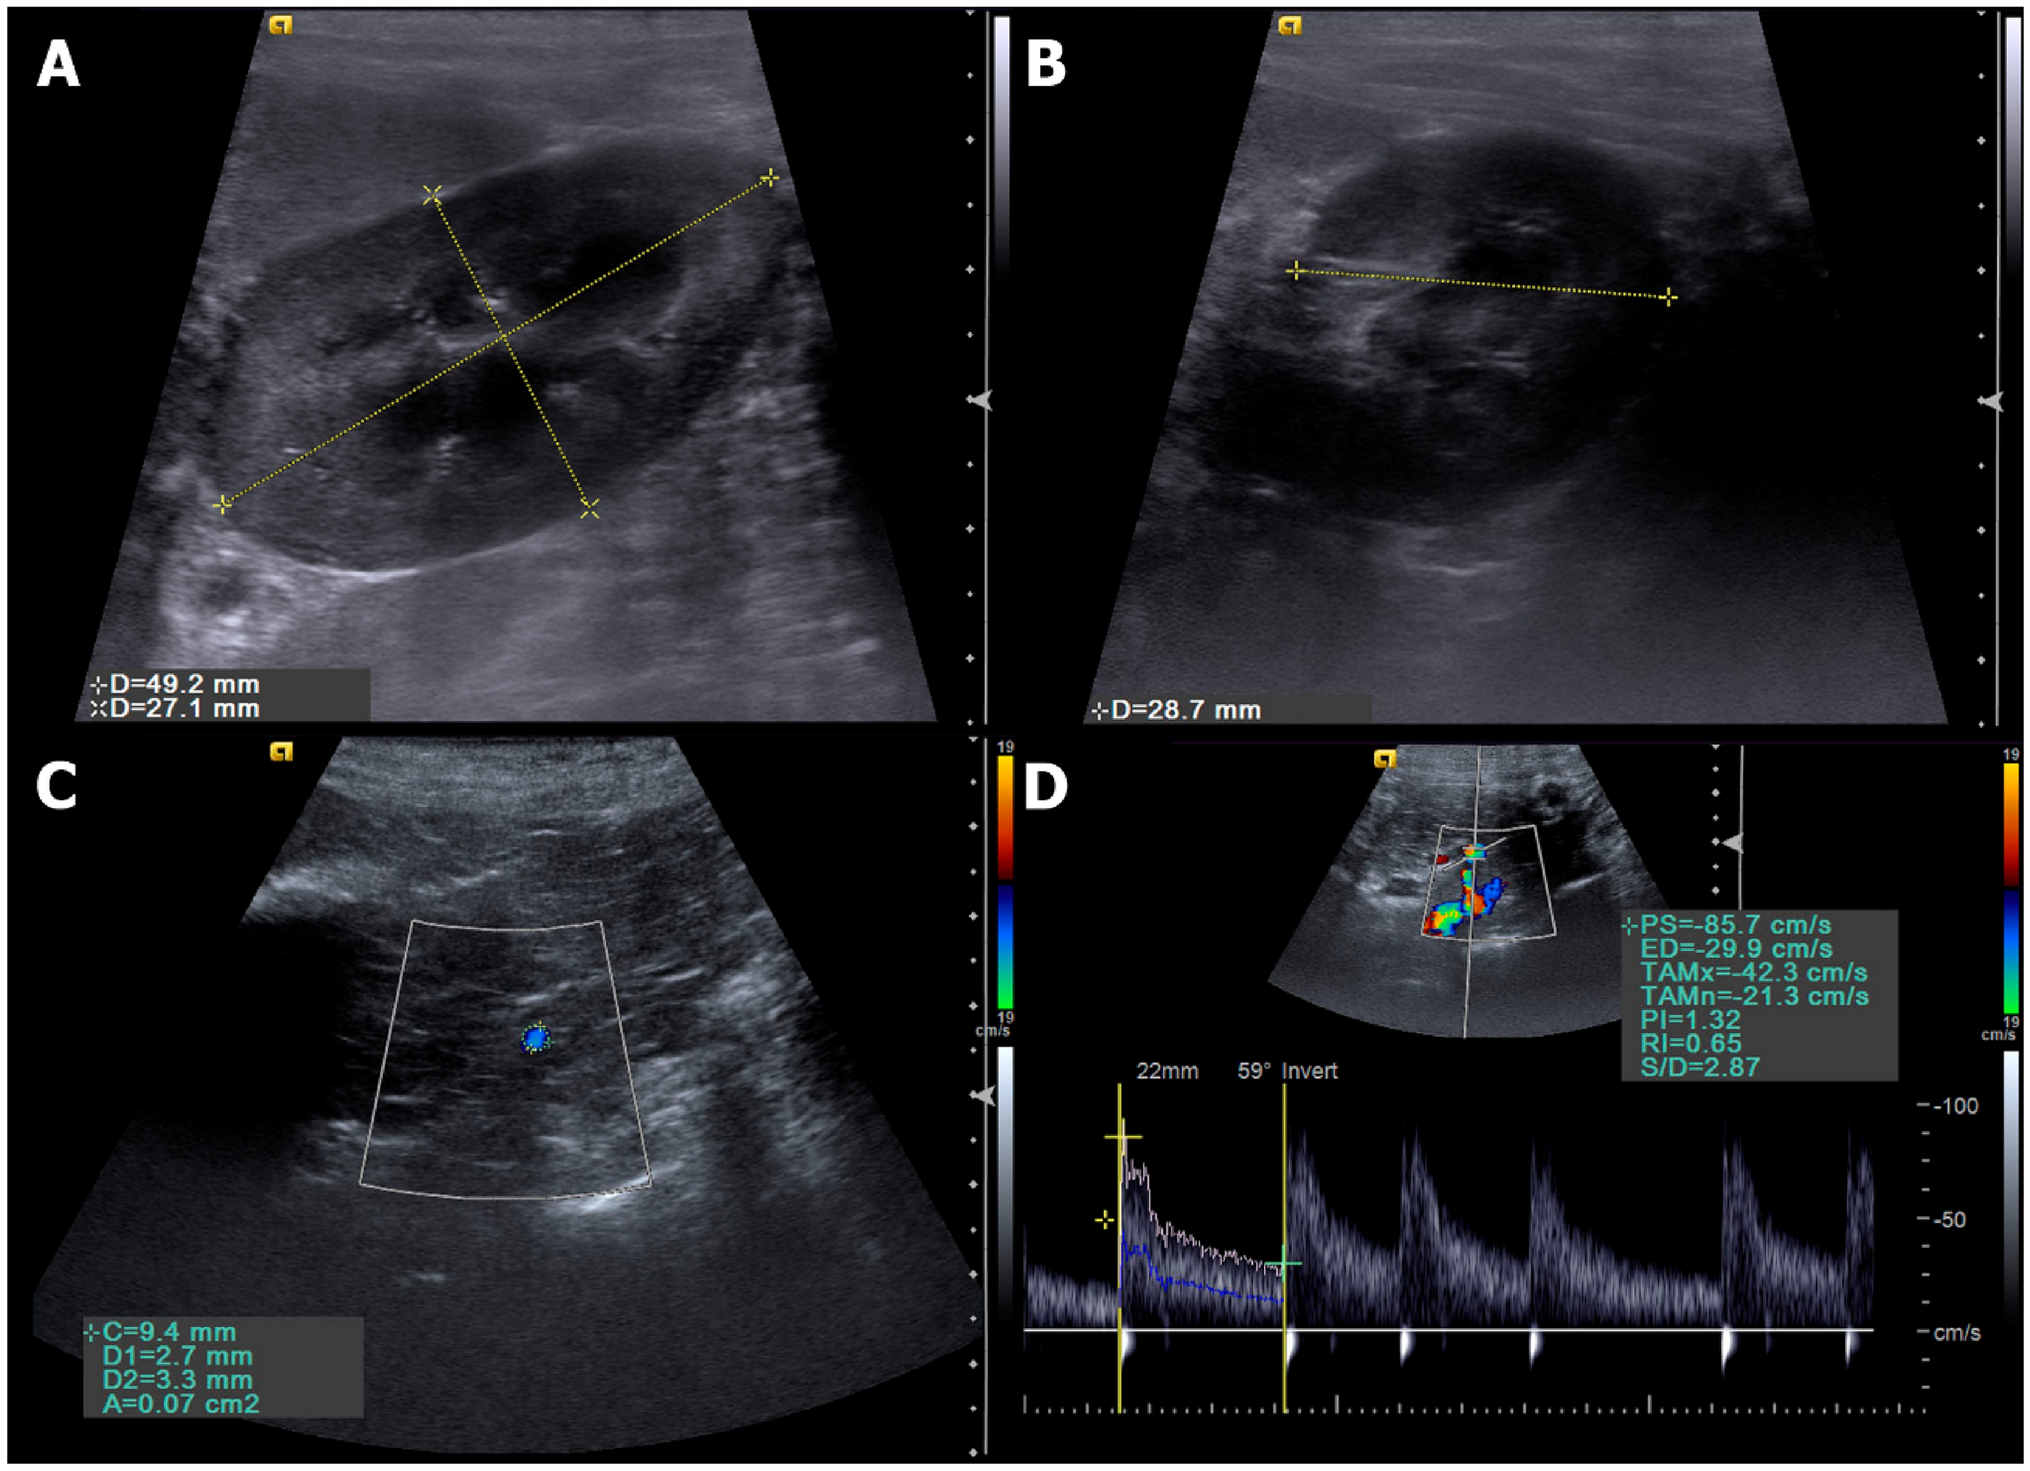

Figure 1

Ultrasonographic evaluations performed. (A) B mode sonographic sagittal view of the left kidney of a bitch delimited by the electronic callipers, measuring the length and height. (B) B mode sonographic transverse view of the left kidney of a bitch at the level of the renal hilum to measure the transverse height. (C) Color Doppler sonographic image of the renal artery (delimitated by the circle calliper) to obtain the vessel area. (D) Pulsed-wave Doppler of the renal artery to obtain the spectral tracing and Doppler flowmetry indices.